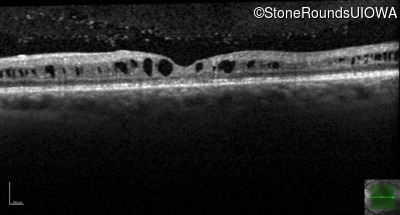

Optical Coherence Tomography - Right - 20/80

Exemplar / OCT Stack

OCT Stack